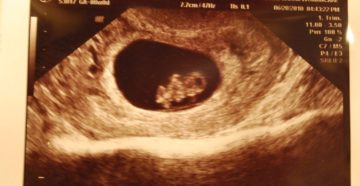

Ктр плода: нормы по неделям и причины отклонений Ультразвуковое исследование – это идеальный метод визуализации…